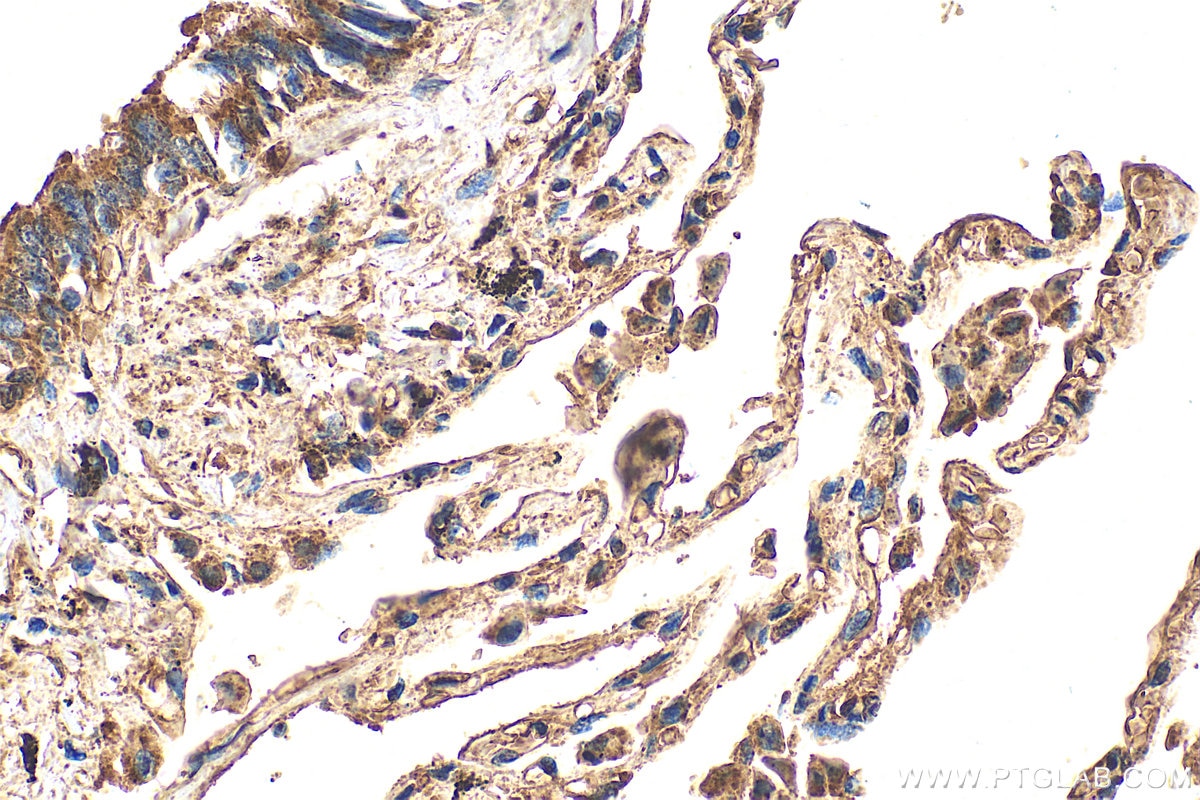

| Positive IHC detected in | human lung tissue Note: suggested antigen retrieval with TE buffer pH 9.0; (*) Alternatively, antigen retrieval may be performed with citrate buffer pH 6.0 |

| Immunohistochemistry (IHC) | IHC : 1:50-1:500 |

31628-1-AP targets VLGR1 in WB, IHC, IP, ELISA applications and shows reactivity with human, mouse samples.

| IHC protocol for VLGR1 antibody 31628-1-AP | Download protocol |